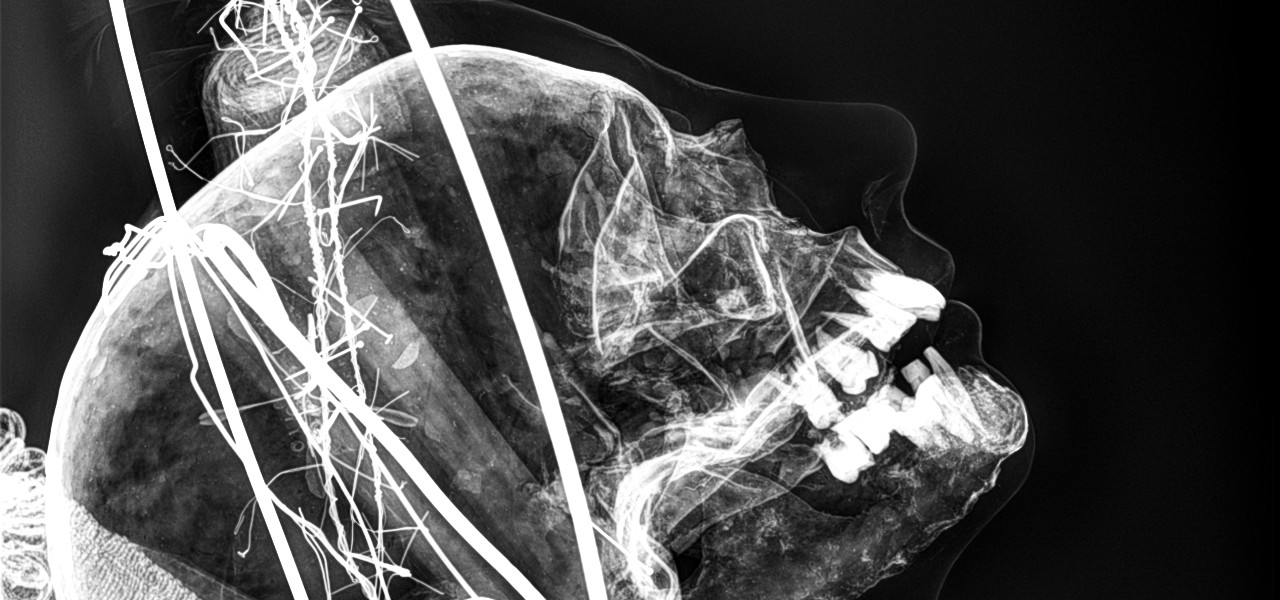

Imagen de San Hermion "un cuerporelicario con restos en su interior" INAH

Entre los Laguenses corre de boca en boca el dicho de que la imagen de San Hermion Mártir era de un cuerpo incorrupto que fue traído a la ciudad por el año de 1790 por el canónigo laguense ...

Leer nota completa

José Luis González Atilano